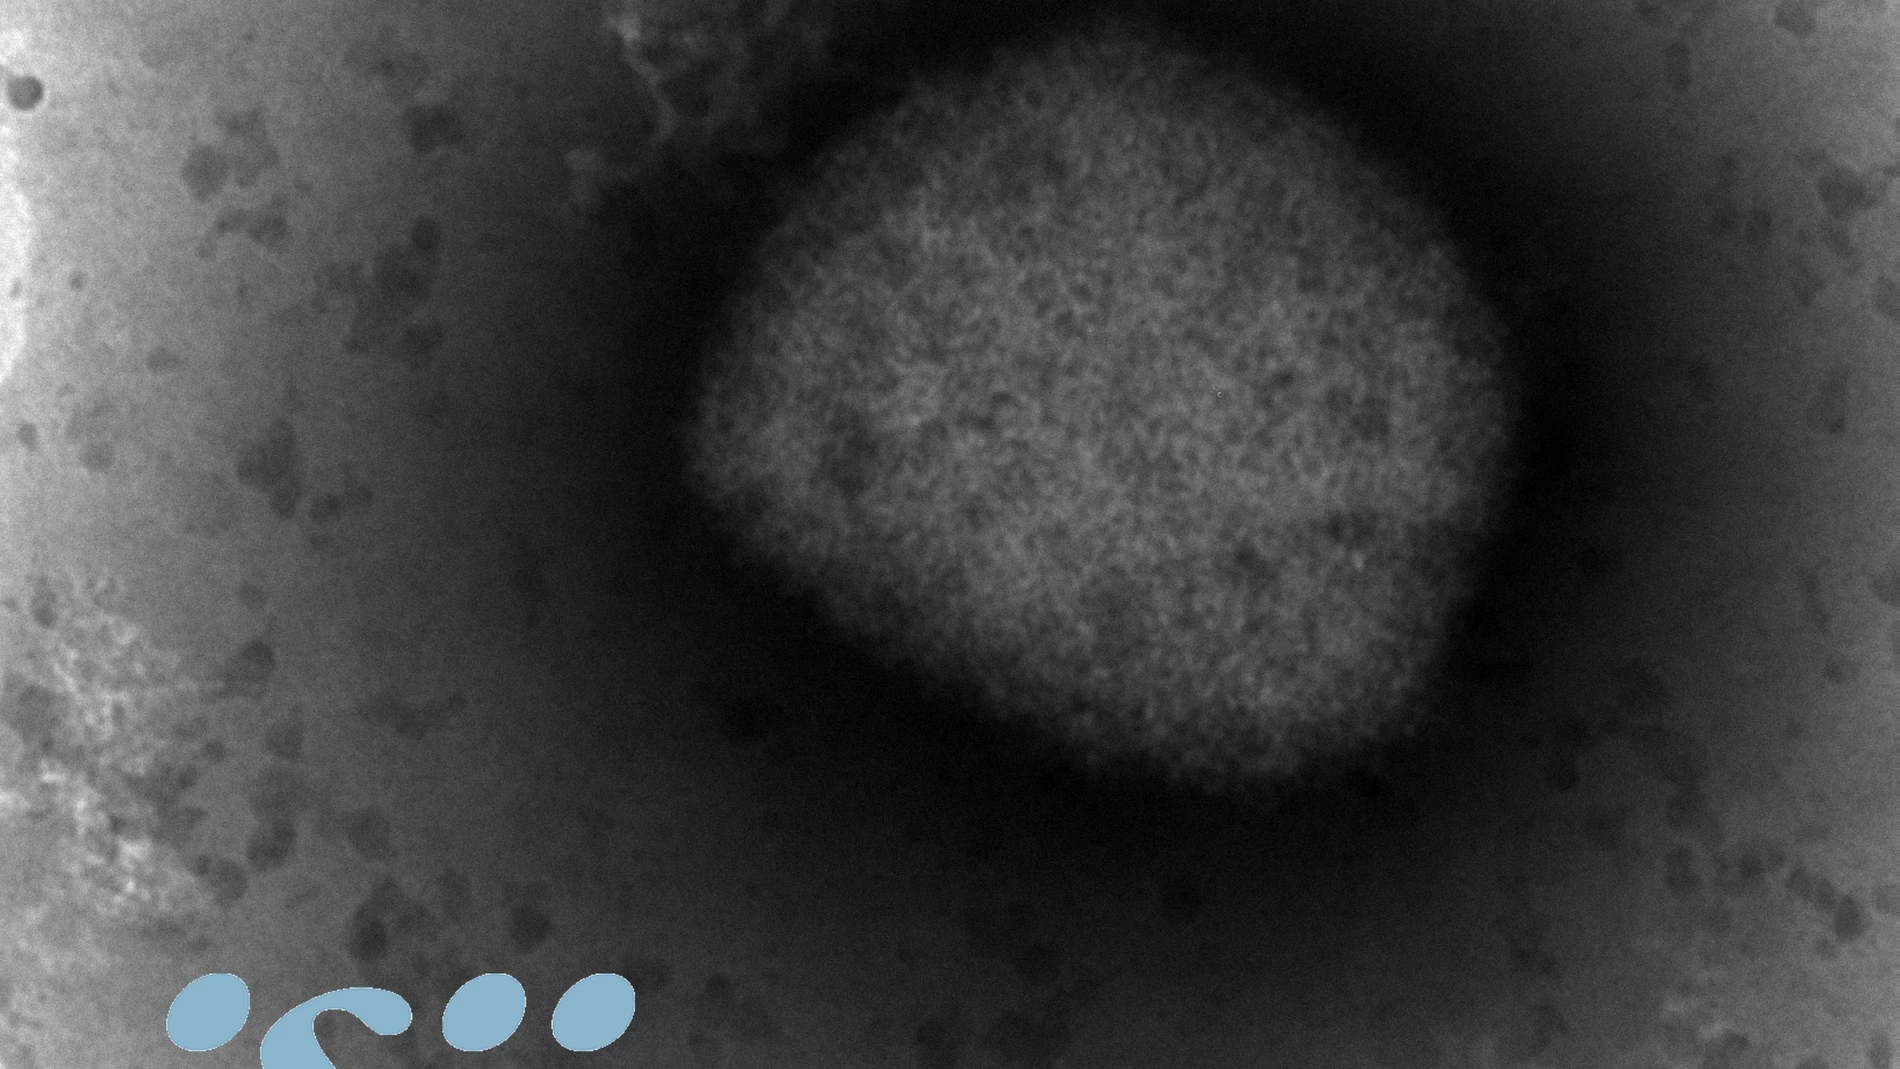

La OMS reconoce el desconocimiento que hay de la viruela del mono

La última alerta sanitaria, la de la viruela del mono, sigue sumando casos. El Ministerio de Sanidad ha confirmado 98 casos positivos, catorce más que ayer. Los nuevos positivos, todos casos leves, siguen aumentando principalmente en la Comunidad de Madrid, en la que han subido a 66 los ya confirmados con ‘monkeypox’, mientras que 36 sospechosos están pendientes de pruebas de laboratorio. En esta cifra, se incluye la infección de una mujer, directamente relacionada con la cadena de transmisión de relaciones entre hombres.

Este viernes, la Organización Mundial de la Salud (OMS) ha reconocido el desconocimiento que actualmente existe sobre muchos aspectos de la viruela del mono, si bien ha asegurado a la sociedad que “no es de preocupar” y que “no es el Covid-19″ y no se transmite tan rápido. En una rueda de prensa durante la celebración de la 75ª Asamblea Mundial de la Salud, los representantes de la organización internacional han informado de que ya se han detectado 200 casos de viruela del mono en todo el mundo, aunque consideran que puede ser la “punta del iceberg” y pueden aparecer “más” en los próximos días. “La cifra de contagiados quizás puede aumentar en los próximos días porque consideramos que estamos realmente al principio de este evento que es inusual y del que todavía hay muy pocos casos exportados a países no endémicos”, han recalcado desde la OMS.

En este sentido, los expertos han comentado que todavía no se sabe si el virus ha cambiado y por eso se está transmitiendo más, “algo poco probable”, o que los contagios se deban al comportamiento humano; al igual que tampoco se conoce cuál es el reservorio animal. “Lo más probable es que este brote se pueda contener con facilidad y, de hecho, tenemos herramientas para ello, aunque primero hay que ver cómo se pueden emplear y estimar las cantidades de terapias que tenemos en todo el mundo”, han enfatizado.

Por ello, desde la OMS se ha instado a los países a que realicen un inventario de las vacunas que disponen contra la viruela porque “no se sabe cuántas” dosis existen en el mundo, aunque el organismo ha asegurado que no es necesario una vacunación masiva de la población. “Algunos países hicieron promesas de donativos y queremos ver cómo se puede acelerar la investigación y producción de vacunas”, han enfatizado los expertos de la OMS en rueda de prensa, para recordar que los tratamientos que existen son en su mayoría experimentales porque eran para la viruela, enfermedad que ya se consideraba erradicada.